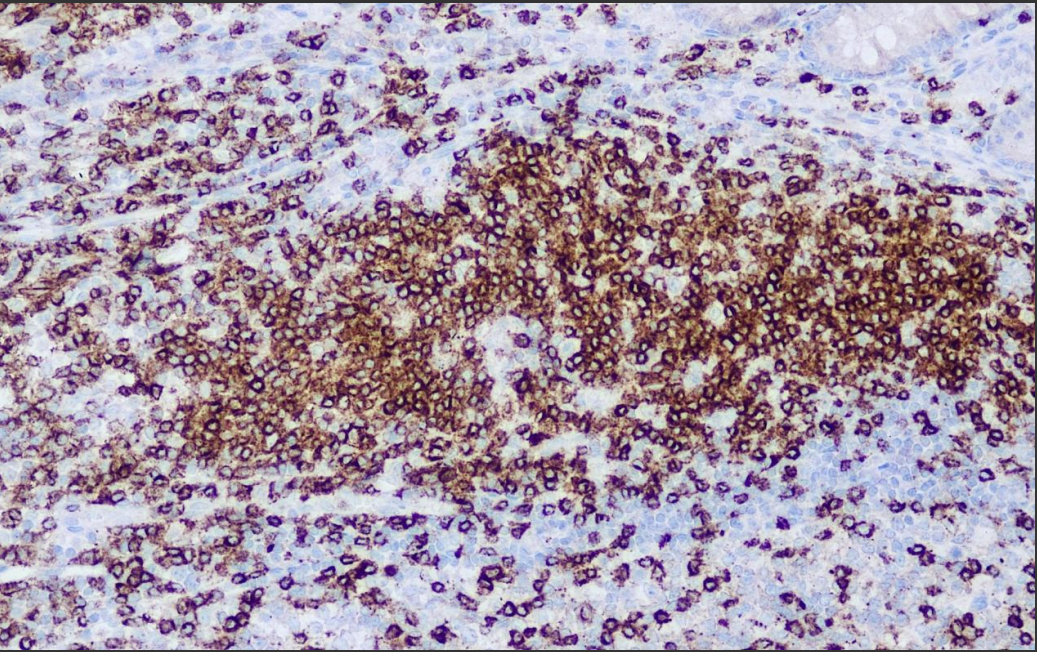

Positive control: tonsils

CD2, also known as LFA-2, Leu-5 or sheep erythrocyte receptor, is a 45-58 kD monomeric molecule, a member of the immune Ig superfamily, which is present on the membrane surface of mature T cells and thymocytes, and is also expressed on NK cells.CD2 molecules are intercellular adhesion molecules as well as signal transduction molecules. This antibody is mainly used to identify T cells and tumors of their origin.

CD2 antibody reagents bind specifically to CD2 molecular antigens. Immunohistochemistry kits containing CD2 antibody reagents are suitable for the precise diagnosis of T-cell and NK-cell related diseases.